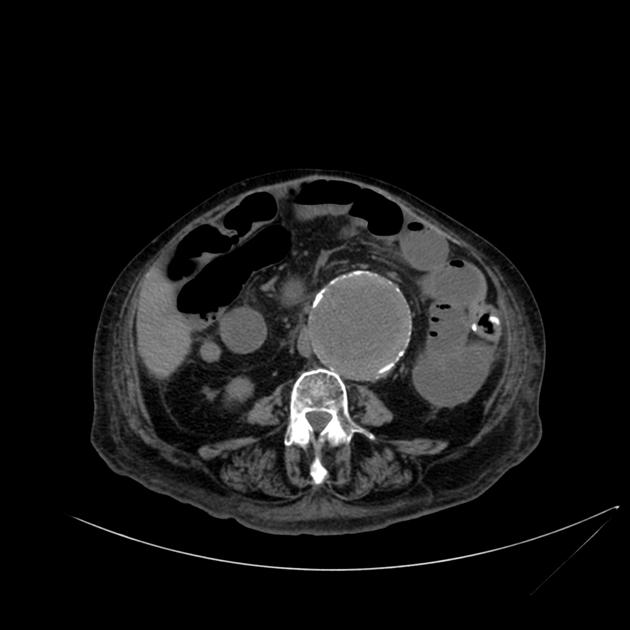

Puzzle 44

What's the Diagnosis?